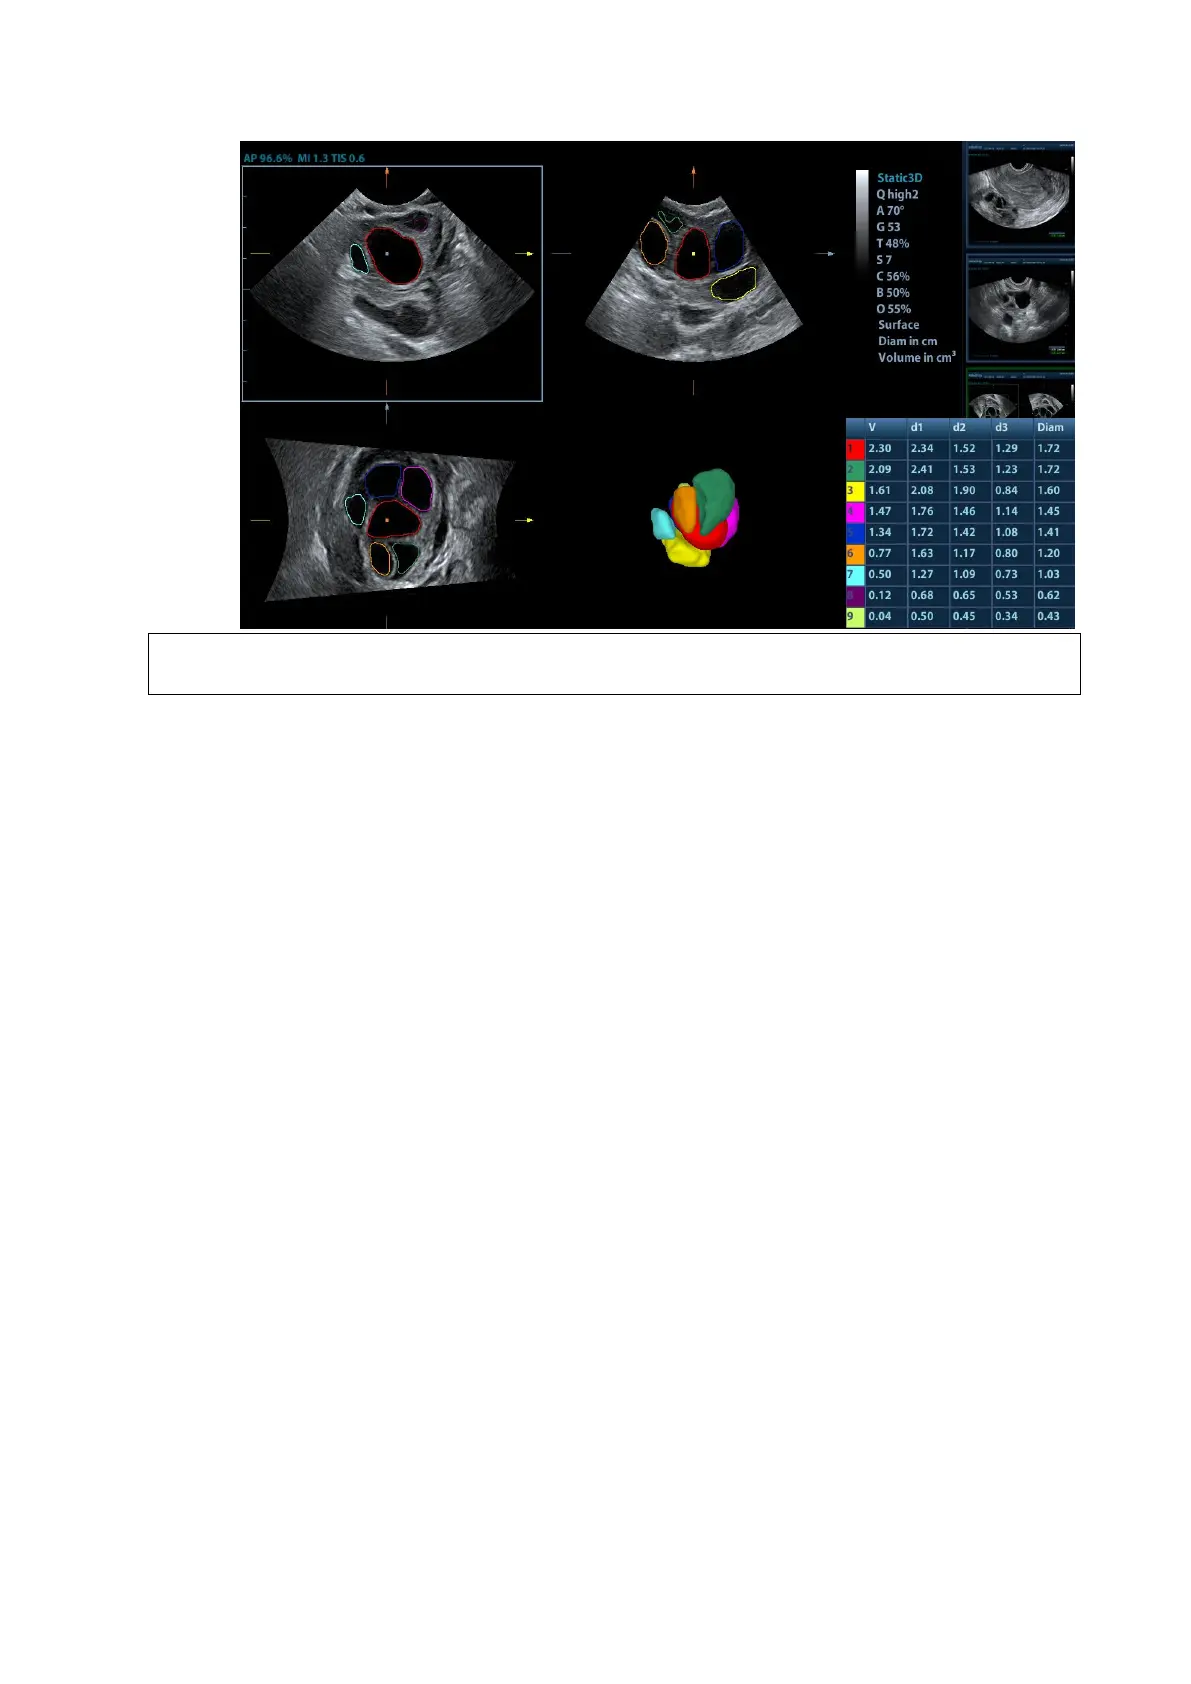

To ensure the correctness of the results, please select an image with clear follicle

boundary when entering Smart FLC.

Touch [Edit] on touch screen to turn on the editing function. It supports dividing, merging, adding

and deleting of the follicle.

Touch [Undo], [Redo] or [Undo All] on touch screen to undo, redo or cancel previous editing.

Measurement

2D related measurement can be performed on MPR. For details, please refer to [Advanced

Volume].

The Smart FLC supports saving single-frame image only, does not support saving multi-frame cine

file.